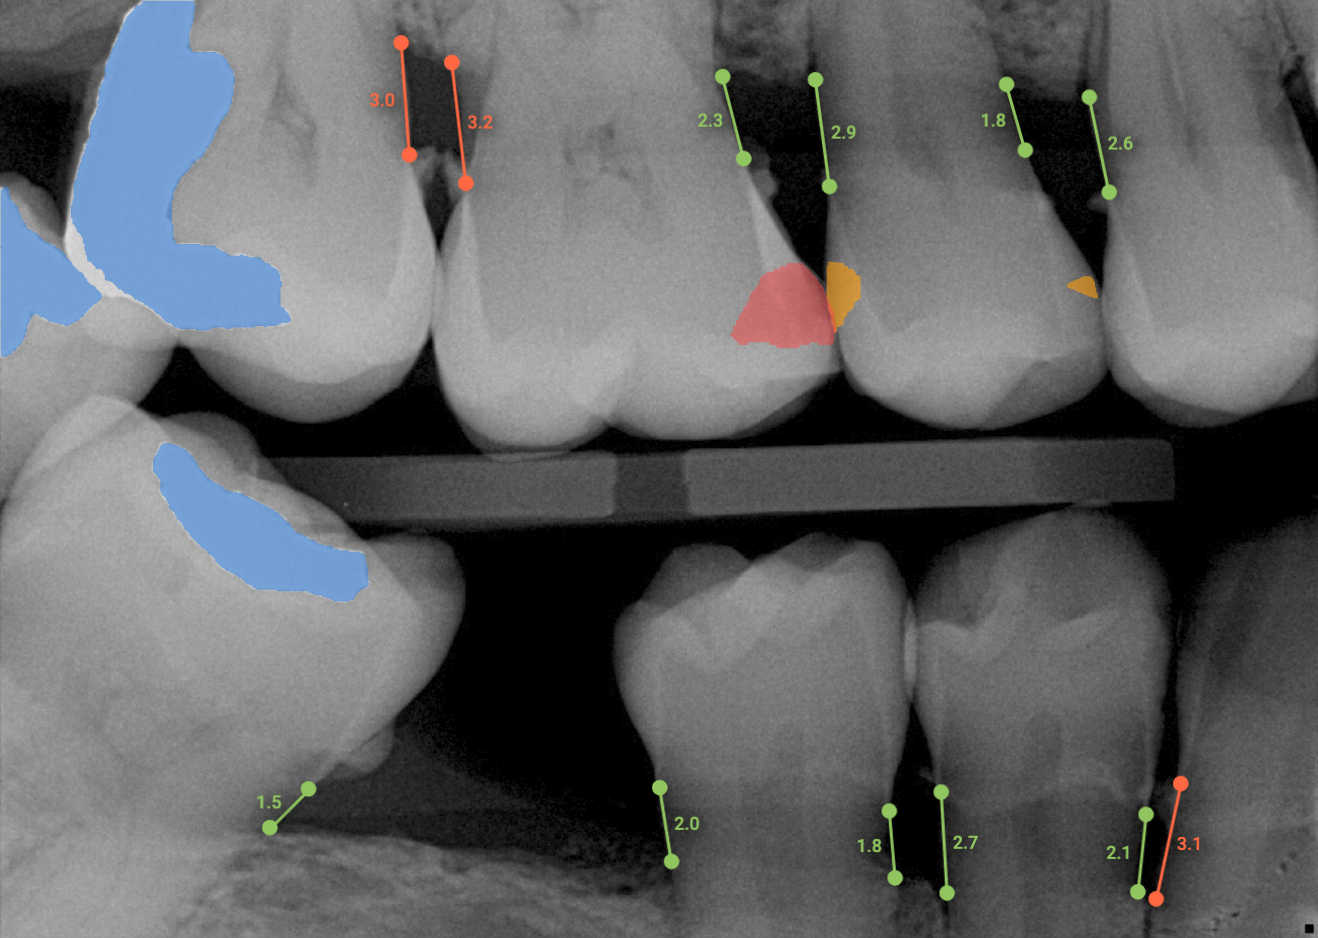

Overjet’s artificial intelligence technology transforms traditional black-and-white X-rays by adding a layer of data that instantly outlines decay (cavities) and measures bone loss. This makes it easy for you to see your results alongside your dentist. It’s like getting a second opinion delivered instantly. With Overjet’s analysis and easy-to-read presentation, you will have the information you need to make an informed decision about your oral health. Together, we’ll review your findings and discuss the best steps to take to achieve your goals.

Overjet’s artificial intelligence technology transforms traditional black-and-white X-rays by adding a layer of data that instantly outlines decay (cavities) and measures bone loss. This makes it easy for you to see your results alongside your dentist.